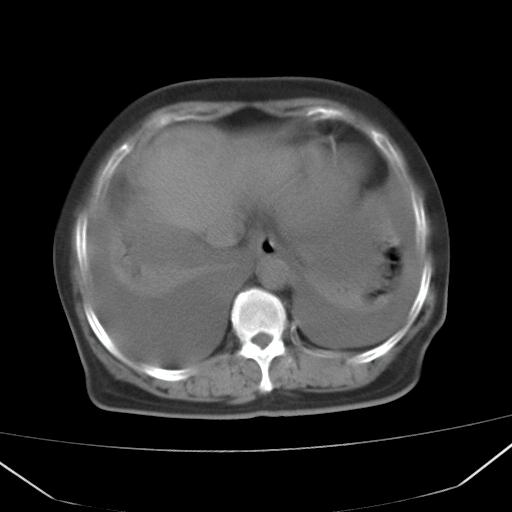

以下是引用jiangjing在2008-4-20 10:43:00的发言:[br]结合病史支持 冠心病[冠状动脉钙化],心功能不全,肺淤血、肺水肿,双侧胸腔与斜裂积液

以下是引用liuyue在2008-4-19 22:25:00的发言:[br]先考虑:1.心衰伴肺水肿、双侧胸腔积液、叶间积液、双下肺不完全性肺不张; [br] 2.冠状动脉粥样硬化。

以下是引用lijuanln在2008-4-19 23:05:00的发言:[br]两侧胸腔积液,肺水肿[br]心包积液[br]提示心衰